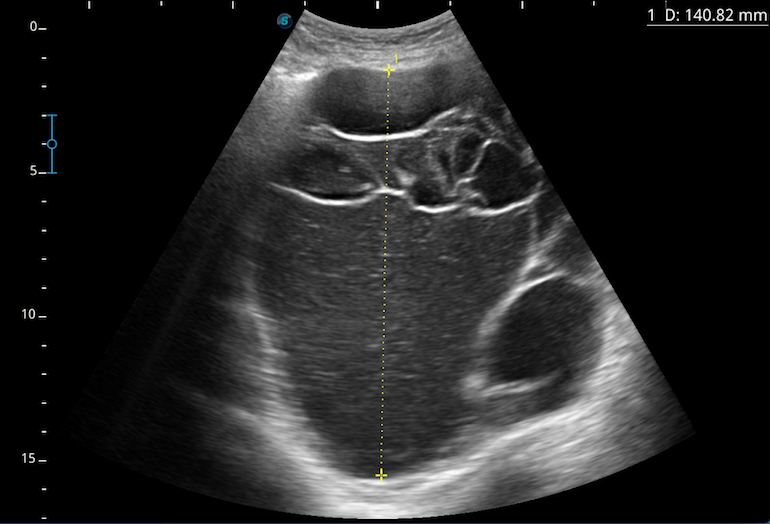

En la exploración se aprecia abdomen distendido, depresible, no doloroso a la palpación. Sin signos de irritación peritoneal. Se palpa masa a nivel de pelvis hasta hipogastrio. Resto de exploración sin alteraciones. Ante estos hallazgos en la exploración se realiza ecografía abdominal en consulta, visualizando una formación con múltiples tabiques que parece depender de ovario derecho y que ocupa toda la pelvis, desplazándose hasta el ombligo. Ante la sospecha de origen ovárico se deriva a la paciente a Ginecología para completar el estudio.

En la ecografía abdominal se evidencia una masa quística, de contornos bien delimitados, multitabicada de unos 15 cm que depende de ovario derecho y que ocupa toda la pelvis, desplazándose hasta hipogastrio.